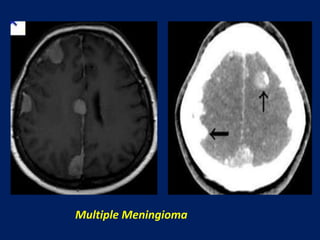

Multiple Meningioma